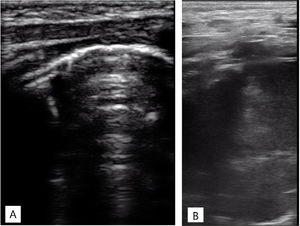

La radiografía de tórax mostraba una opacidad completa en el lóbulo superior derecho (fig. 1), mientras que las ecografías pulmonares seriadas eran normales (fig. 2A). La ecografía torácica realizada desde el plano supraclavicular mostraba una consolidación bien definida sugestiva de masa torácica (fig. 2B y vídeo 1) que se evidencia en la TAC (fig. 3). La biopsia confirma el diagnóstico de neuroblastoma congénito.

Ecografía torácica realizada con sonda lineal de alta frecuencia. A)Plano longitudinal a nivel de campo pulmonar anterior, superior derecho. Adecuado deslizamiento pleural, buena aireación en todos los campos pulmonares, con patrón de líneas A y puntuación de Brat de 0 puntos. B)Plano supraclavicular derecho. Consolidación sin broncograma aéreo ni captación en el doppler con borde profundo bien definido y redondeado de 6cm de diámetro máximo.

El 5% de los neuroblastomas se manifiestan en periodo neonatal1, estando localizados hasta el 15% en el tórax2, pudiendo causar dificultad respiratoria y estridor. La sospecha inicial de bronquiolitis complicada con neumonía o atelectasia, basada en los hallazgos radiológicos, fue reconsiderada tras la normalidad de la ecografía, motivando la evaluación de otras regiones. La discrepancia entre las pruebas de imagen debe hacernos sospechar otros diagnósticos3. Aunque las masas torácicas son raras en neonatos, una consolidación radiológica con patrón ecográfico pulmonar normal puede sugerir dicho diagnóstico.